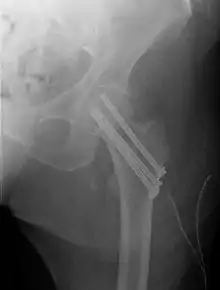

Closed reduction may not be satisfactory and open reduction then becomes necessary.[42] The use of open reduction has been reported as 8-13% among pertrochanteric fractures, and 52% among intertrochanteric fractures.[43] Both intertrochanteric and pertrochanteric fractures may be treated by a dynamic hip screw and plate, or an intramedullary rod.[42]

The fracture typically takes 3–6 months to heal. As it is only common in elderly, removal of the dynamic hip screw is usually not recommended to avoid unnecessary risk of second operation and the increased risk of re-fracture after implant removal. The most common cause for hip fractures in the elderly is osteoporosis; if this is the case, treatment of the osteoporosis can well reduce the risk of further fracture. Only young patients tend to consider having it removed; the implant may function as a stress riser, increasing the risk of a break if another accident occurs.